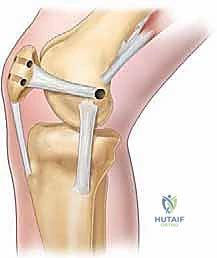

- Anchor Placement: We will now place two small, fully threaded suture anchors into the medial border of the patella.

- Drill Hole Preparation: Using a drill guide, create pilot holes for the anchors. Aim for the superior and inferior aspects of the MPFL footprint on the patella.

> Drill under constant direct visualization. Ensure the drill bit does not penetrate the articular surface of the patella. The patella is a relatively thin bone, and intra-articular penetration can cause significant chondral damage. - Anchor Insertion: Insert the suture anchors securely into the drilled holes, ensuring they are flush with the bone surface.

- Pearl: Predrill the anchor holes carefully. Test the security of the anchors after insertion with a gentle tug. They should be absolutely rock-solid.

Intraoperative view illustrating the placement of suture anchors into the medial patellar facet, preparing for MPFL reattachment.

Close-up view of the suture anchors securely placed into the patella, with sutures ready for passage through the avulsed MPFL.